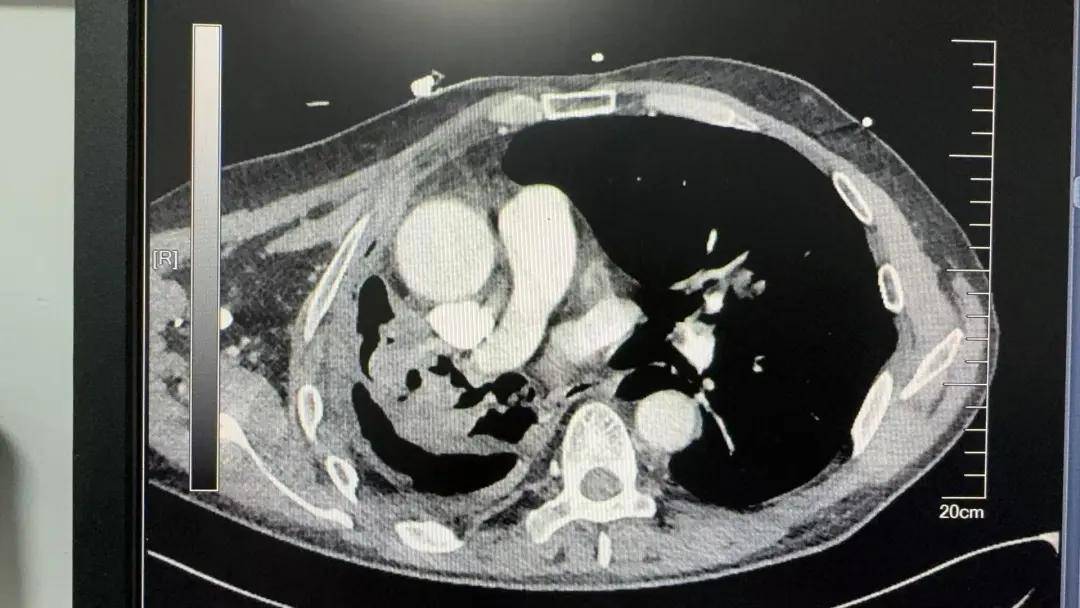

患者的冠状动脉重度狭窄,主动脉根部膨出一直径约5.7厘米的动脉瘤,主动脉瓣大量反流,一旦发生主动脉瘤破裂就会危及生命,这种情况同样需要手术治疗。

经胸外科、心血管外科、重症医学科、麻醉科多学科会诊,专家团共同为患者制定出一套"先行右全肺切除、择期心血管外科手术"的序贯治疗方案。

由于患者胸膜广泛黏连增厚,手术游离过程中很容易出现大出血,谨慎操作的同时还需避免牵拉刺激心脏而导致的血压波动、循环不稳定。麻醉团队密切监测血压变化,控制血压波动。